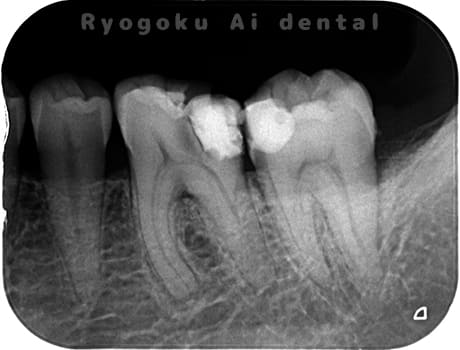

Case07

-

- 原因

- 慢性根尖性歯周炎(16・17・15部)

- 治療内容

- マイクロエンド(3歯分)

- 治療費用

- 308,000円(3歯分)※被せ物を除く

右上の違和感が取れないとのことで来院された患者さんです。ファイルという器具が歯の根の中で折れていることを説明し、マイクロスコープを使用した根管治療を提案し、治療を行いました。折れたファイルも取り除くことができ、現在の経過は良好です。

<リスク・副作用>

術後は痛み、腫れ、痺れなどの副作用が生じる場合があります。症状が再発する可能性があります。